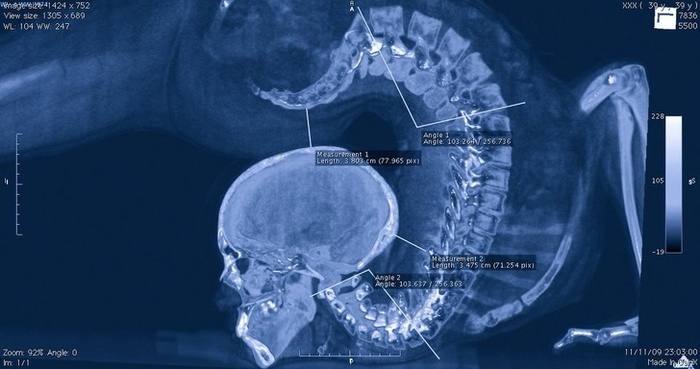

Рентгеновский снимок акробата